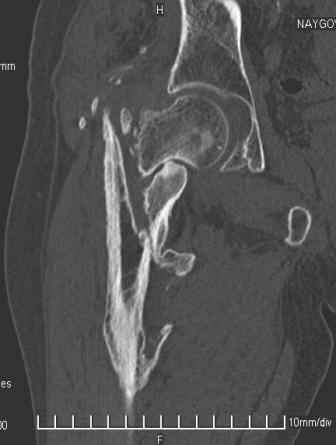

Больной Н. 44 года травма 1,5 года назад июнь 2008 года чрез-под вертельный перелом правого бедра. Во время лечения у больного развился алк. делирий, проводилось консервативное лечение перелома.

Беспокоят боли, укорочение конечности.Укорочение 3 см. Ногу поднимает, сгибание ограничено, ротационные движения в полном объеме.На КТ перелом сросся за счет костной мозоли.Что делать?

Уважаемый Глеб, боли из-за ложного сустава шейки бедра. Сращения там нет.

Уважаемый Глеб! Укорочение наверное побольше, да и наружно-ротационная установка скорее всего присутствует. Суставная щель прекрасная, головка живее всех живых. Ратую за подвертельную с латерализацией: исключает нарушение механической оси («исключает вальгус в коленe»), максимально удлиняет без натяжения m.iliacus. Для иллюстрации остеотомия-переделка (слава богу не автопеределка) у мужчины 65 лет.